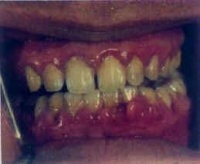

肥大性龈炎

肥大性龈炎(Hypertrophic Gingivitis)牙龈组织受到长期的局部刺激所引起的慢性炎症,表现以牙龈明显的炎性肿胀增生为特征。病变可累及附着龈。多见于青春期,以上下颌前牙唇侧牙龈为好发部位。

牙龈肿胀肥大,呈深红色或暗红色,组织松软,探诊易出。牙龈乳头球状突起。肿胀的牙龈常可覆盖前牙唇的1/3或更多。由于牙龈肥大,使龈沟加深而形成龈袋,袋内易藏食物,细菌易滋生,自洁作用差,故炎症加重,可有深性分泌物。若身体抵抗力降低时,可出现单发或多发性的龈脓肿,特别以龈乳头区较多见。

自觉症状可有刺激性牙龈出血、发胀、口臭等。病变后期,因纤维增生而使牙龈质地较为坚韧,炎症也有减轻,又称增生性龈炎